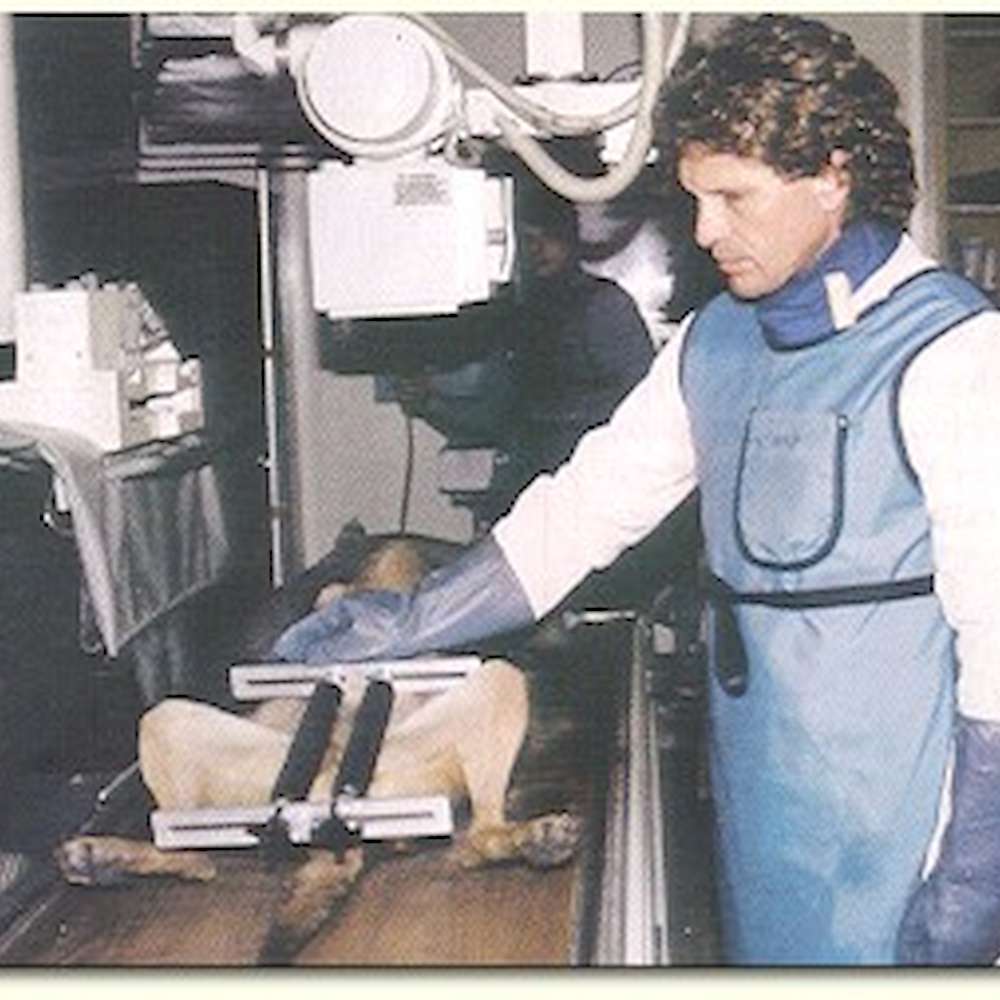

Radiographs submitted to the OFA should follow the American Veterinary Medical Association recommendations for positioning. This view is accepted world wide for detection and assessment of hip joint irregularities and secondary arthritic hip joint changes. To obtain this view, the animal must be placed on its back in dorsal recumbency with the rear limbs extended and parallel to each other. The knees (stifles) are rotated internally and the pelvis is symmetric. Chemical restraint (anesthesia) to the point of relaxation is recommended. For elbows, the animal is placed on its side and the respective elbow is placed in an extreme flexed position.

Chemical restraint (anesthesia) is not required by OFA but chemical restraint to the point of muscle relaxation is recommended. With chemical restraint optimum patient positioning is easier with minimal repeat radiographs (less radiation exposure) and a truer representation of the hip status is obtained.

The distraction view and compression view are used to obtain accurate and precise numerical measurements of joint laxity and conformation. The hip-extended view is used to diagnose osteoarthritis using criteria similar to the OFA and other hip screening organizations. Precise positioning of the dog by trained certified PennHIP members is imperative and any radiographs that do not conform to prescribed positioning are rejected and must be repeated.